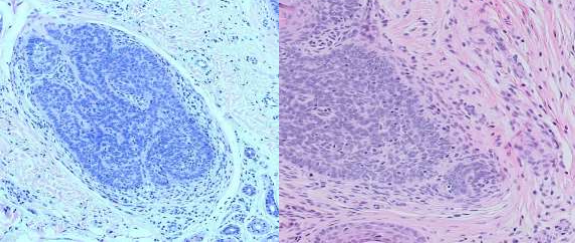

A 39-year-old male presented to the dermatology clinic of a Veterans Affairs medical center with a cystic nodule of the left medial eyebrow measuring 0.8 x 0.7 cm (figure 1). The patient was known to have CCS. His father, paternal aunt, and paternal grandfather had been diagnosed with Brooke-Spiegler syndrome (diagram 1). After presenting with multiple trichoepitheliomas, he had tested positive for a heterozygous pathogenic variant (c.2288-2289del p.Phe 763) of CYLD NM-015247.2CYLD. With this history, the clinical differential for this eyebrow lesion was cylindroma versus spiradenoma. Microscopic examination of the excision specimen revealed a well-circumscribed, dermal-based adnexal proliferation with areas recapitulating each part of the normal hair follicle: the?infundibulum, inner root sheath, outer root sheath, matrix, and bulb (figure 2.A&B). Areas resembling the infundibular portion of the hair follicle contained cystic cell aggregates lined by stratified squamous epithelium with a granular layer and filled with “basket-weave” orthokeratin (figure 2.C). Areas resembling the suprabulbar portion of the hair follicle showed clear cells as seen in the external root sheath and eosinophilic cells as seen in the internal root sheath (figure 2.D&E). Areas resembling the bulbar portion of the hair follicle showed immature basaloid cells and papillary mesenchymal bodies (figure 2.F&G). The lesion was uniformly circumscribed and without cytologic atypia, so a diagnosis of PF was rendered.

Figure 2.A&B Dermal-based adnexal proliferation of cystic and solid structures with follicular differentiation towards all components of the hair follicles (4X, 10X)

Figure 2.C Infundibular/isthmus differentiation (20x)

Figure 2.D&E Area resembling the suprabulbar portion of the hair follicle (20x)

Figure 2. F&G Area resembling bulbar areas with immature basaloid cells and papillary mesenchymal bodies